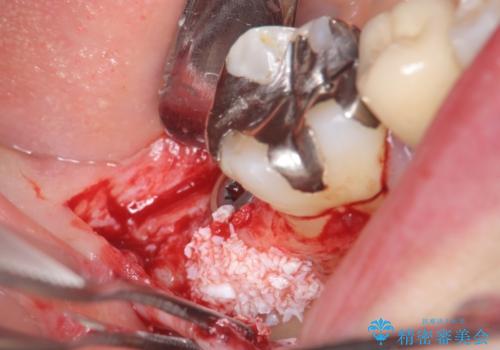

- 右下7番にインプラント治療を行った症例です。

CT撮影を行い状態を確認後、インプラント(ストローマン)の埋入(一次手術)を行いました。

インプラントと骨の定着を待った後に二次手術を行い、カスタムアバットメント、オールセラミッククラウンによる補綴を行いました。